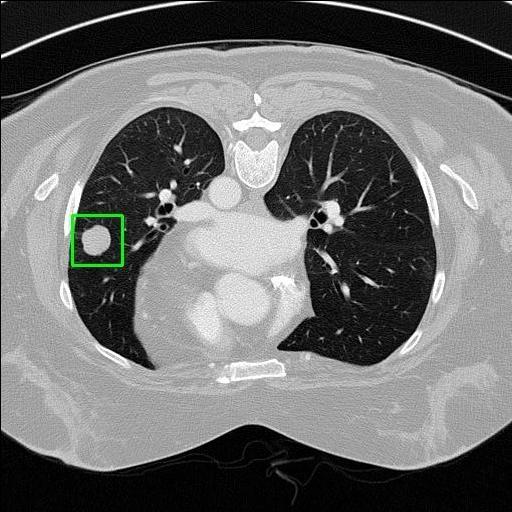

We developed an AI-based system using deep learning models for analyzing lung CT scans to detect and classify pulmonary nodules. We chose the YOLOv11 architecture for its enhanced object detection capability and adapted it specifically for medical imaging, incorporating pixel-level precision and severity classification.

Classification into three severity levels with colored bounding boxes.

Distinguishing between similar-looking benign and malignant nodules posed classification difficulty.

Designed a severity classification system that categorizes nodules into null, moderate, and severe using colored bounding boxes, assisting in rapid clinical decision-making.